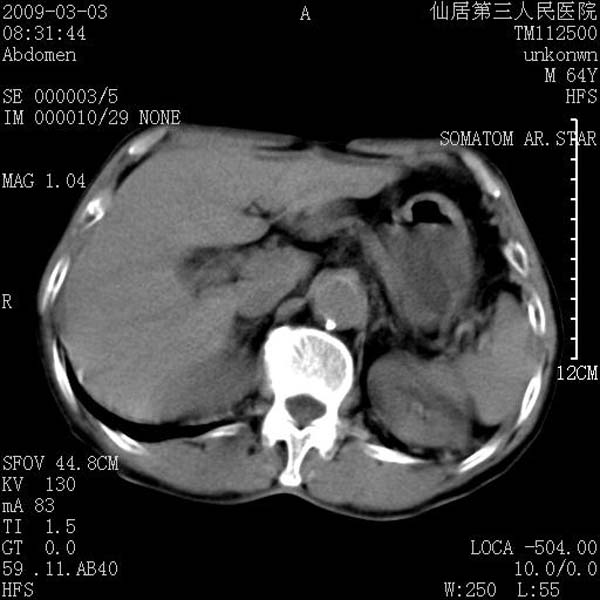

标题: CT18469:男性,64y,体检B超示肝脏低回声肿块,有胃溃疡手术 [打印本页]

患者,男性,64y,体检b超示肝脏低回声肿块,有胃溃疡手术史。

考虑----胃肠道间质瘤可能性大

从平扫及增强的特点来看,支持肝脏腺瘤并出血。

考虑胃间质瘤可能性大。

胃肠道间质瘤!

ct值呢?感觉没强化,象囊性。

考虑肝静脉韧带裂区良性占位性病变(囊肿?)。

考虑肝囊肿并出血可能性大.

考虑高密度囊肿可能性大